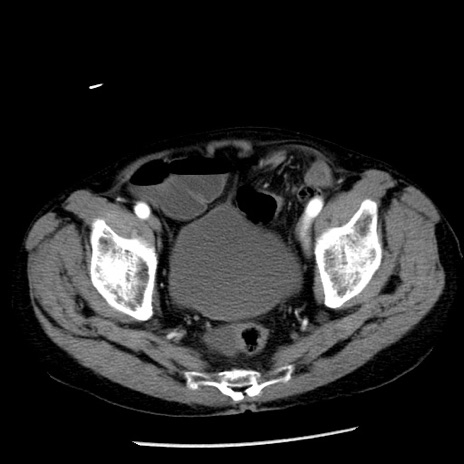

症例26(横断像)

【症例】80歳代男性

【主訴】嘔吐

【現病歴】昨晩2回嘔吐あり、今朝になっても嘔吐あり。来院。

【既往歴】胃潰瘍

【身体所見】意識清明、BT 37.6℃、BP 166/95mmHg、HR 100bpm、SpO2 97%、腹部:平坦・軟、腸蠕動音聴取良好、圧痛なし。

【データ】WBC 21900、CRP 1.46